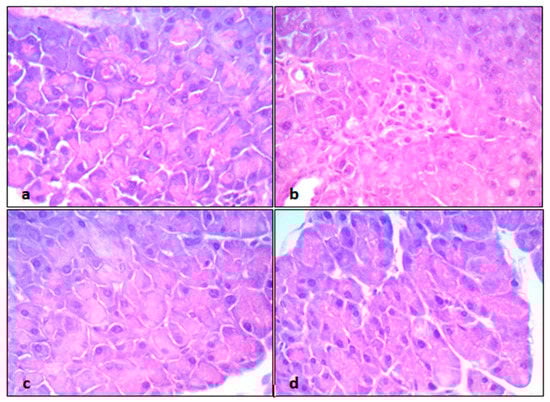

2.4. Histopathological Examination and Analysis

| Groups | Grades | Mean Scoring Grades for Pancreatic Histopathological Changes | |||

| 1 | 2 | 3 | 4 | ||

| Control | 6 | 1 | 1 | 0 | 1.37 ± 0.26 |

| CP-intoxicated | 0 | 1 | 4 | 3 | 3.37 ± 0.18 a |

| CP + EPO (5 mg/kg) | 0 | 6 | 1 | 1 | 2.5 ± 0.26 ab |

| CP + EPO (10 mg/kg) | 6 | 1 | 1 | 0 | 1.5 ± 0.26 bc |

| (b) | |||||